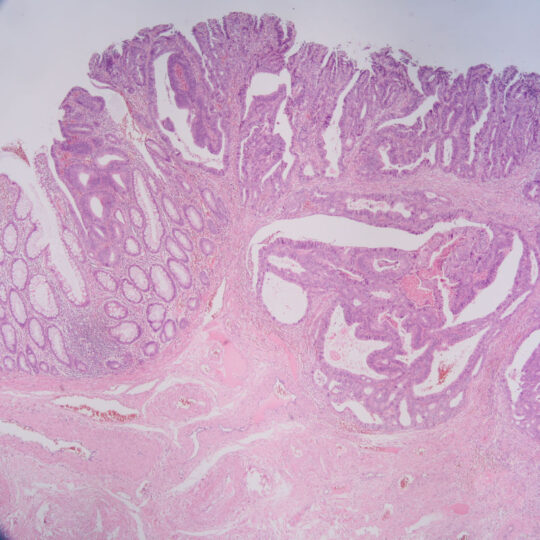

Na bioptickom úseku sa vykonáva štandardná diagnostika nádorových a nenádorových lézií rôznych orgánov, počnúc ochoreniami gastrointestinálneho traktu, ženského a mužského pohlavného systému, močového systému, ochorení hlavy a krku, nádorových ochorení CNS, kože, mäkkých tkanív a štítnej žľazy. Vyšetruje sa fixovaný materiál s použitím štandardných (HE), špeciálnych (Fe, PAS, Melaním VG, Ret…) a imunohistochemických farbiacich metód.

Biopsia (histológia) je vyšetrenie orgánov, tkanív, buniek získaných odberom z tela človeka počas operácie, alebo iného medicínskeho výkonu, prípadne samovoľným vylúčením.

Základom bioptickej diagnostiky je mikroskopické vyšetrenie tkanív, ktoré musia byť spracované na rezy tenké niekoľko mikrometrov. Túto činnosť zabezpečuje bioptické laboratórium. Od kvality jeho práce vo veľkej miere závisí aj kvalita konečnej diagnostiky. Ide o pomerne náročnú procedúru vyžadujúcu čas a profesionálnu zručnosť.